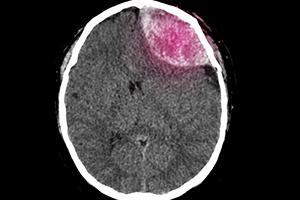

Commonly referred to as a brain bleed, a nursing home subdural hematoma happens when blood pools between the brain and the skull. This is one of the most severe forms of brain injury and a leading cause of wrongful death in the elderly.

A subdural hematoma, referred to as a brain bleed, occurs when blood pools between the brain and the skull. This condition is caused by a tear in the veins of the brain’s protective covering, leading to blood leakage. There are several types of subdural hematoma, each with distinct forms and causes.